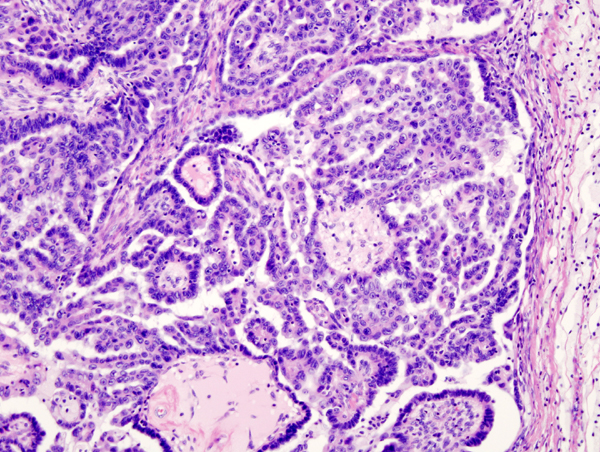

Bildgebung

© wikipedia.org/KGH, CC BY 3.0